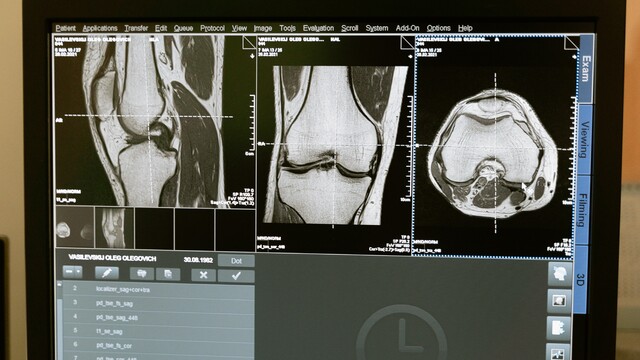

Za predĺženie kostí sú zodpovedné rastové platničky. Tieto štruktúry sa nachádzajú na koncoch vašich kostí, kde ukladajú vrstvy chrupavky, ktoré vápenatejú a časom tvrdnú. Keď sa tento postupný proces skončí, prestaneme rásť. Platničky tvrdnú a kosti sa ďalej nerozširujú. Stále však môžu hrubnúť, vďaka čomu sú odolnejšie.